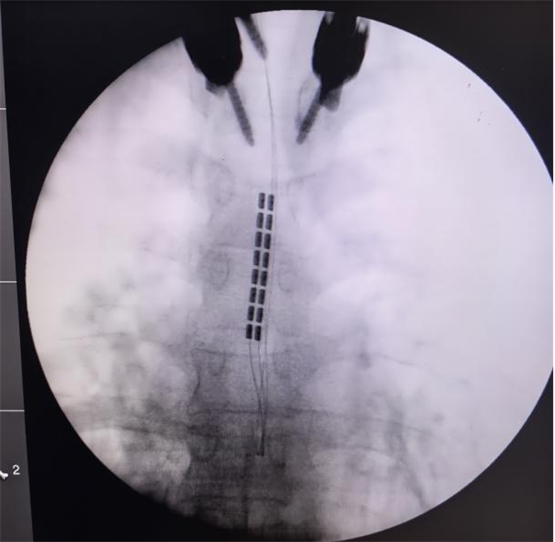

经过严格的术前讨论,团队决定为孙女士施行颈段脊髓电刺激(SCS)植入术。手术由陈菊祥教授主刀,在C臂X光机精准引导下,将刺激电极植入颈髓(C2-C4水平)硬膜外腔的中线位置。

为避免对患者脊髓功能造成任何医源性损伤,团队在术中全程采用了影像导航系统,以及多模式神经电生理监测,包括连续脑电图(EEG)、体感诱发电位(SSEP)等,实时监控神经系统功能状态,为手术安全上了“双保险”。“手术精度要求达到毫米级,确实是刀尖上起舞,“陈菊祥教授如此形容,”术后我立刻查看了影像,确认电极位置精准。”